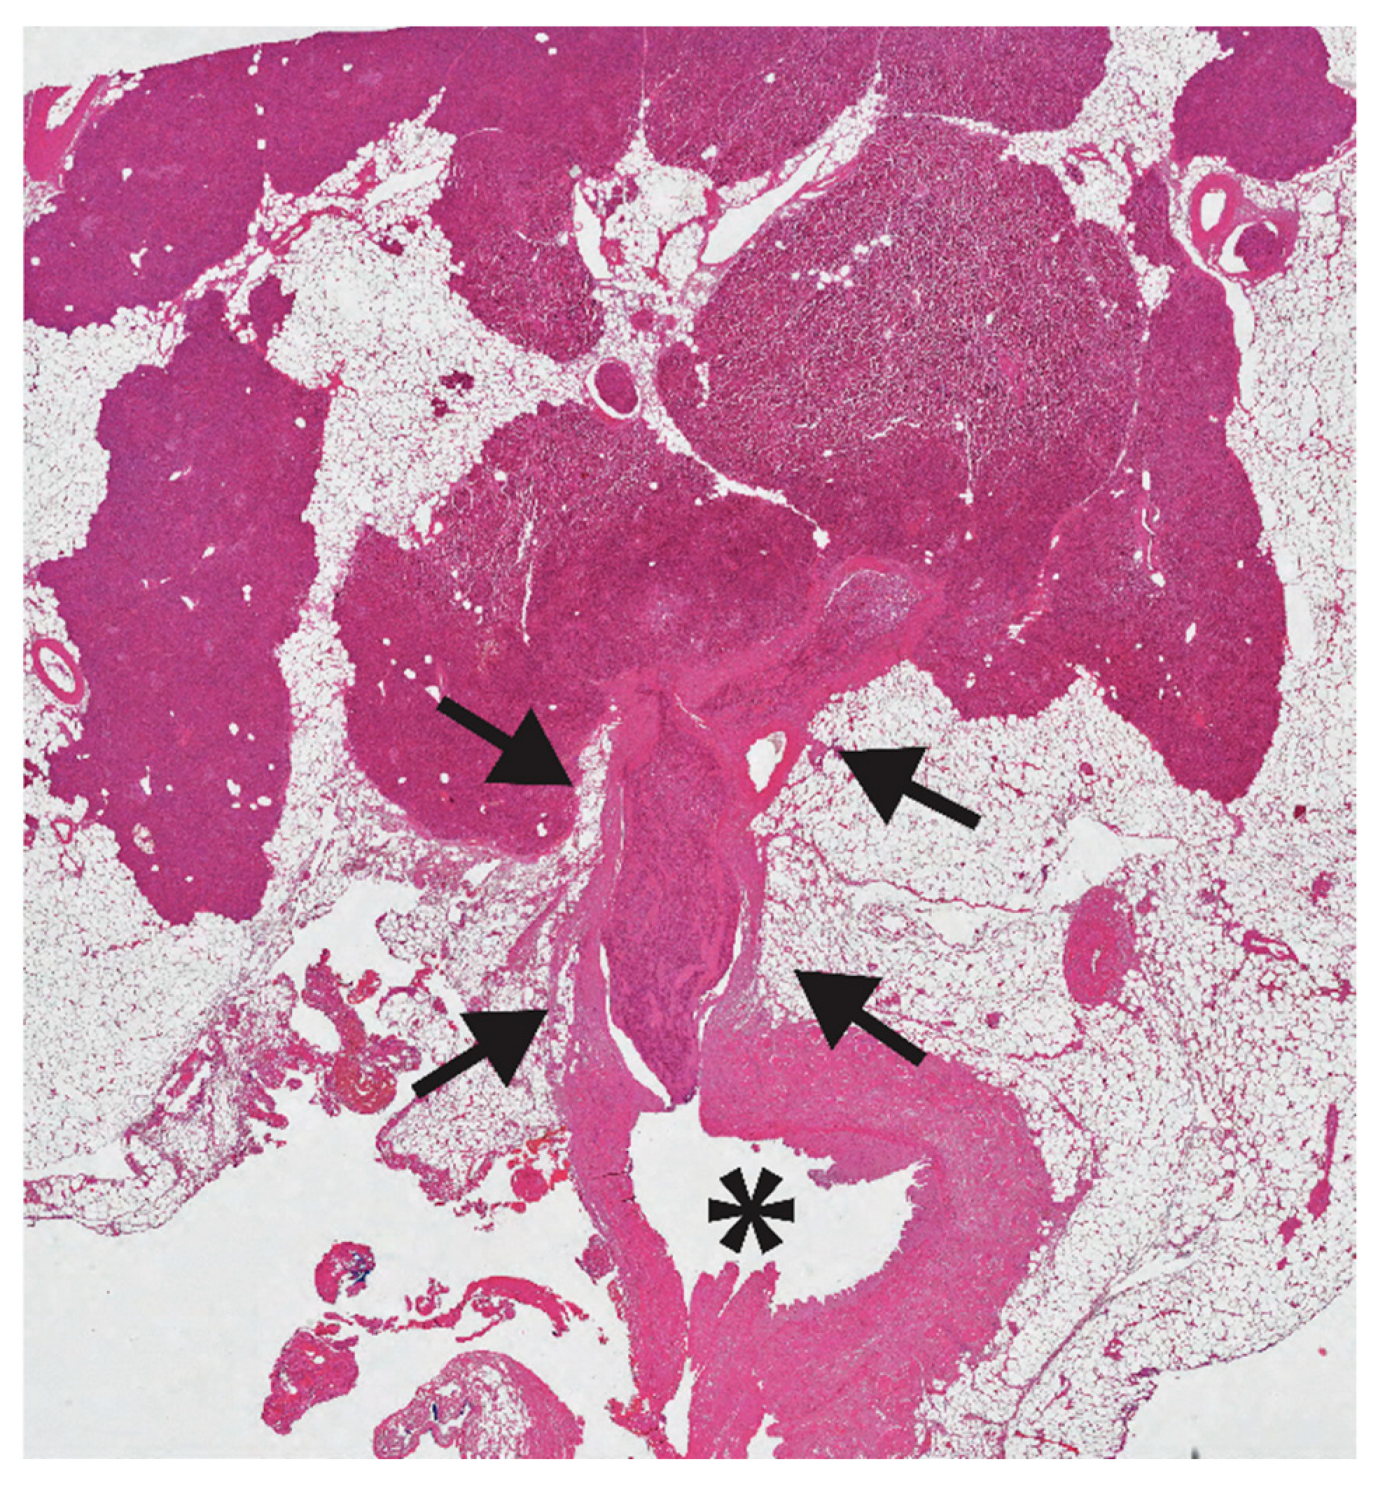

Figure 2.

A huge neoplastic thrombus is seen (black arrows) in a branch of the splenic vein (asterisk). This 43-years old man underwent distal pancreatectomy for a 2.3 cm panNET, Ki67 3%, with loss of Death Domain Associated Protein (DAXX) nuclear expression (hematoxylin eosin stain; 20×).